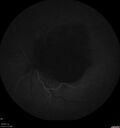

Last additions - Ruptured Macroaneurysm and BRAO 81 year old female The vision in the left eye declined a few days ago. Her coumadin level was high recently. She had stopped the coumadin for eye surgery. Then when she went back on the coumadin her levels were high (3.1).

Ruptured Retinal Arterial Macroaneurysm - Submacular hemorrhage and BRAO95 views81 year old female with vision loss for a few days. Coumadin was high with INR at 3.1 VA 6/200Dec 21, 2024